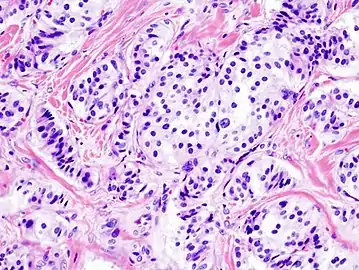

Pathology of pancreatic endocrine tumour (insulinoma). | |

- Pancreatic insulinoma